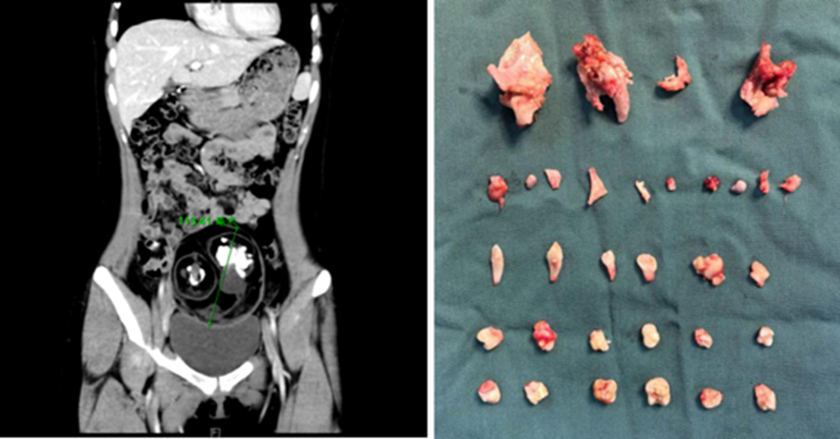

Bệnh nhân cho biết cơn đau xuất hiện đột ngột ở vùng bụng dưới bên phải khi đang tập thể dục tại nhà. Cơn đau kéo dài, không thuyên giảm khiến cô phải nhanh chóng đến bệnh viện để kiểm tra. Kết quả siêu âm khiến cả bệnh nhân lẫn bác sĩ bất ngờ khi trong bụng cô có một khối u đường kính khoảng 12cm, thậm chí trên hình ảnh còn thấy thấp thoáng cấu trúc giống răng và xương.

Thông qua một đường rạch nhỏ khoảng 2cm tại rốn - vị trí có nếp gấp tự nhiên - các bác sĩ đã bóc tách và lấy trọn khối u kích thước 12cm ra ngoài. Khi kiểm tra bên trong khối u, chính đội ngũ y tế cũng không khỏi bất ngờ khi phát hiện tới 24 chiếc răng với hình dạng khác nhau, cùng với mô xương có đường kính gần 5cm.